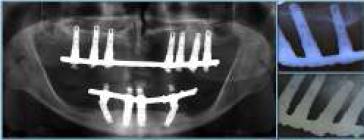

Una vez transcurrido el tiempo necesario para la oseointegración (2 meses en el maxilar inferior y 6 en el superior) se conectan los implantes (ISQ entre 65 a 70 en todos los implantes en mediciones perpendiculares entre sí para cada implante, a excepción de implante en relación a 2,5 que solo logra un ISQ de 45) utilizando pilares cónicos, rectos en los implantes mediales y con angulación de 30◦ en los implantes distales. Además, se confeccionan las prótesis provisorias fijas sobre los implantes, indicando a la paciente las técnicas de cepillado y mantenimiento correspondiente. En el momento de la conexión se pierde un implante en relación con la pieza 2,5, situación que al no afectar en el pronóstico del tratamiento se decide no insistir en su repocisión. Una vez estabilizados los tejidos blandos (fig. 3) se realiza la toma de impresión con silicona por adición Panasil Putty e Initial Contact Light® (Kettenbach GmbH & Co.KG, Eschenburg, Alemania) con cubeta funcional mediante la técnica de cubeta abierta, ferulizando los transfers de impresión con resina bis-acrílica Luxatemp® (DMG, Hambrug, Alemania). Además, se toma impresión a los provisionales y se realiza toma de registros. Los modelos de trabajo y los obtenidos de las prótesis provisorias fueron escaneados en el laboratorio para realizar el diseño asistido por ordenador (CAM) de las subestructuras metálicas para las rehabilitaciones protésicas (fig. 4), utilizando como referencia las prótesis transitorias, respetando así los espacios protésicos necesarios y obtener, de esta manera, una rehabilitación funcional y estética. Las subestructuras diseñadas se confeccionaron mediante sinterizado láser, lo que permitió controlar de forma precisa el diseño de los socavados y perlas de retención para acrílico (fig. 5). La prueba de las barras en boca muestra un ajuste pasivo de estas, lo que se corrobora con la toma de radiografías panorámica y periapicales, observando el correcto asentamiento protésico tanto maxilar como mandibular (fig. 6). Una vez verificado el ajuste pasivo de las subestructuras, se continúa con la confección de las prótesis híbridas, con el recubrimiento acrílico de las barras, logrando resultados satisfactorios, tanto funcionales como estéticos, al devolver el soporte labial y reponer los elementos dentarios perdidos (figs. 7 y 8). Una vez finalizadas las prótesis estas se torquean a 15 N y se sellan las chimeneas con teflón y resina compuesta (Permaflow Pink®, Ultradent Walladent y Amellogen Plus®, Ultradent Walladent, EE. UU.) (fig. 9).

En relación con el ajuste pasivo de la subestructura sobre los implantes, en donde es deseable evitar desajustes que puedan ocasionar fallos en la oseointegración de estos, el sinterizado láser ha demostrado ajustes más precisos que los obtenidos mediante cera perdida15, por lo que podría mejorar el éxito a largo plazo de restauraciones múltiples sobre implantes, respetando las propiedades mecánicas que los estándares ISO para aleaciones metálicas10.